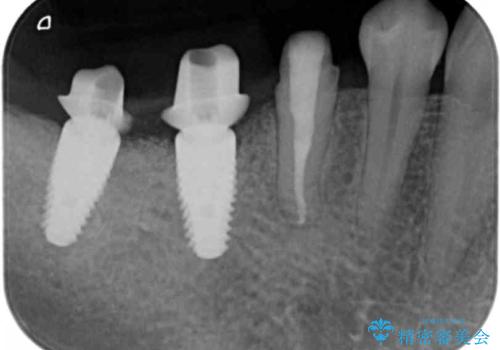

精査したところ、右下の奥歯(右下6)は割れており保存不可能な状態でした。

患者様のご希望により、右下大臼歯2本(右下76)のインプラント治療、右下小臼歯(右下5)の根管治療及び補綴治療を行いました。

割れていた歯の周囲組織の炎症が強く、骨の厚みが薄かったため、インプラント埋入時に骨増生(GBR)を行いました。

インプラントの種類:ストローマン BLT